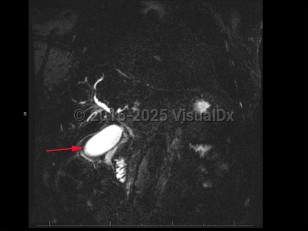

Cholangiocarcinoma refers to biliary tree malignancies, primarily adenocarcinomas, of epithelial cell origin. They are typically categorized as intrahepatic, perihilar, or distal.

Cholangiocarcinomas often present insidiously; symptom onset often coincides with biliary duct obstruction leading to jaundice, pruritus, or cholangitis. Other less specific signs and symptoms include unexplained weight loss, lethargy, abdominal pain, nausea, and anorexia.

Patients with cholangiocarcinoma will often have elevations in their liver function tests (total and direct bilirubin) and liver enzymes (aspartate transaminase [AST], alanine transaminase [ALT], alkaline phosphatase), although these are nonspecific findings. Elevations in cancer antigen (CA) 19-9, a tumor marker, can be suggestive of cholangiocarcinoma but are limited by nonspecificity. Diagnosis typically requires tissue sampling via endoscopic retrograde cholangiopancreatography (ERCP) with brushing.